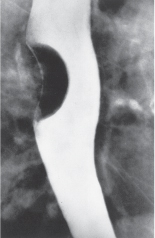

16. A patient presents with dysphagia and undergoes a barium swallow. Based on the image in Fig. 25-10, the most likely diagnosis is

Answer: D

A barium swallow is the most useful method to demonstrate a leiomyoma of the esophagus (Fig. 25-10). In profile, the tumor appears as a smooth, semilunar, or crescent-shaped filling defect that moves with swallowing, is sharply demarcated, and is covered and surrounded by normal mucosa. (See Schwartz 9th ed., p 874.)

FIG. 25-10.